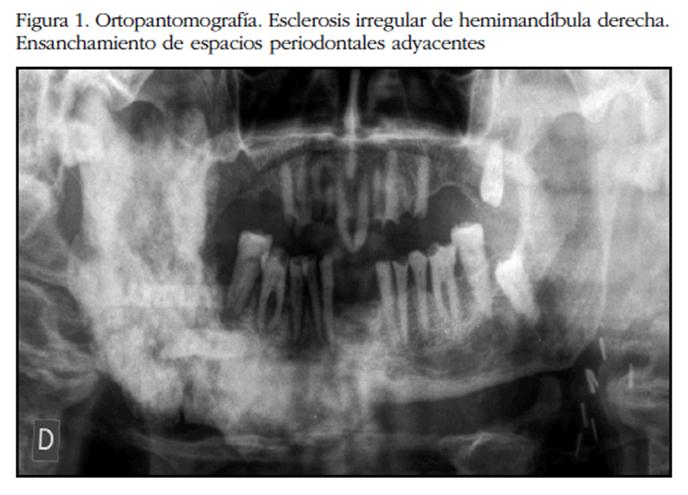

Varón de 77 años, ex-fumador de 20 paquetes-año, ex-bebedor de 7 unidades de bebida estándar/día hasta hace 2 años, y con antecedentes de hipertensión arterial, ictus isquémico y estenosis carotídea izquierda intervenida. Como tratamiento médico habitual refiere atorvastatina, valsartán, hidroclorotiazida y clopidogrel. Es diagnosticado de adenocarcinoma de próstata en estadío IV Gleason 3+4, con valores de PSA de 110,47 ng/mL y fosfatasa alcalina (FA) de 142 U/L iniciales, y metástasis óseas en vértebras C7 y D1. Los niveles séricos de calcio, fósforo y hormona paratiroidea están dentro de la normalidad. Inicia tratamiento con bloqueo androgénico completo. 19 meses después refiere clínica de flemón hemifacial derecho, con abombamiento de ambas corticales de la rama ascedente de mandíbula ipsilateral (Figura 1) y sin ulceración de mucosa oral a la exploración. La anatomía patológica proporciona un nuevo diagnóstico de EOP en fase mixta, sin datos sugestivos de malignidad (Figura 2). No hay sospecha de afectación en otras regiones del esqueleto.